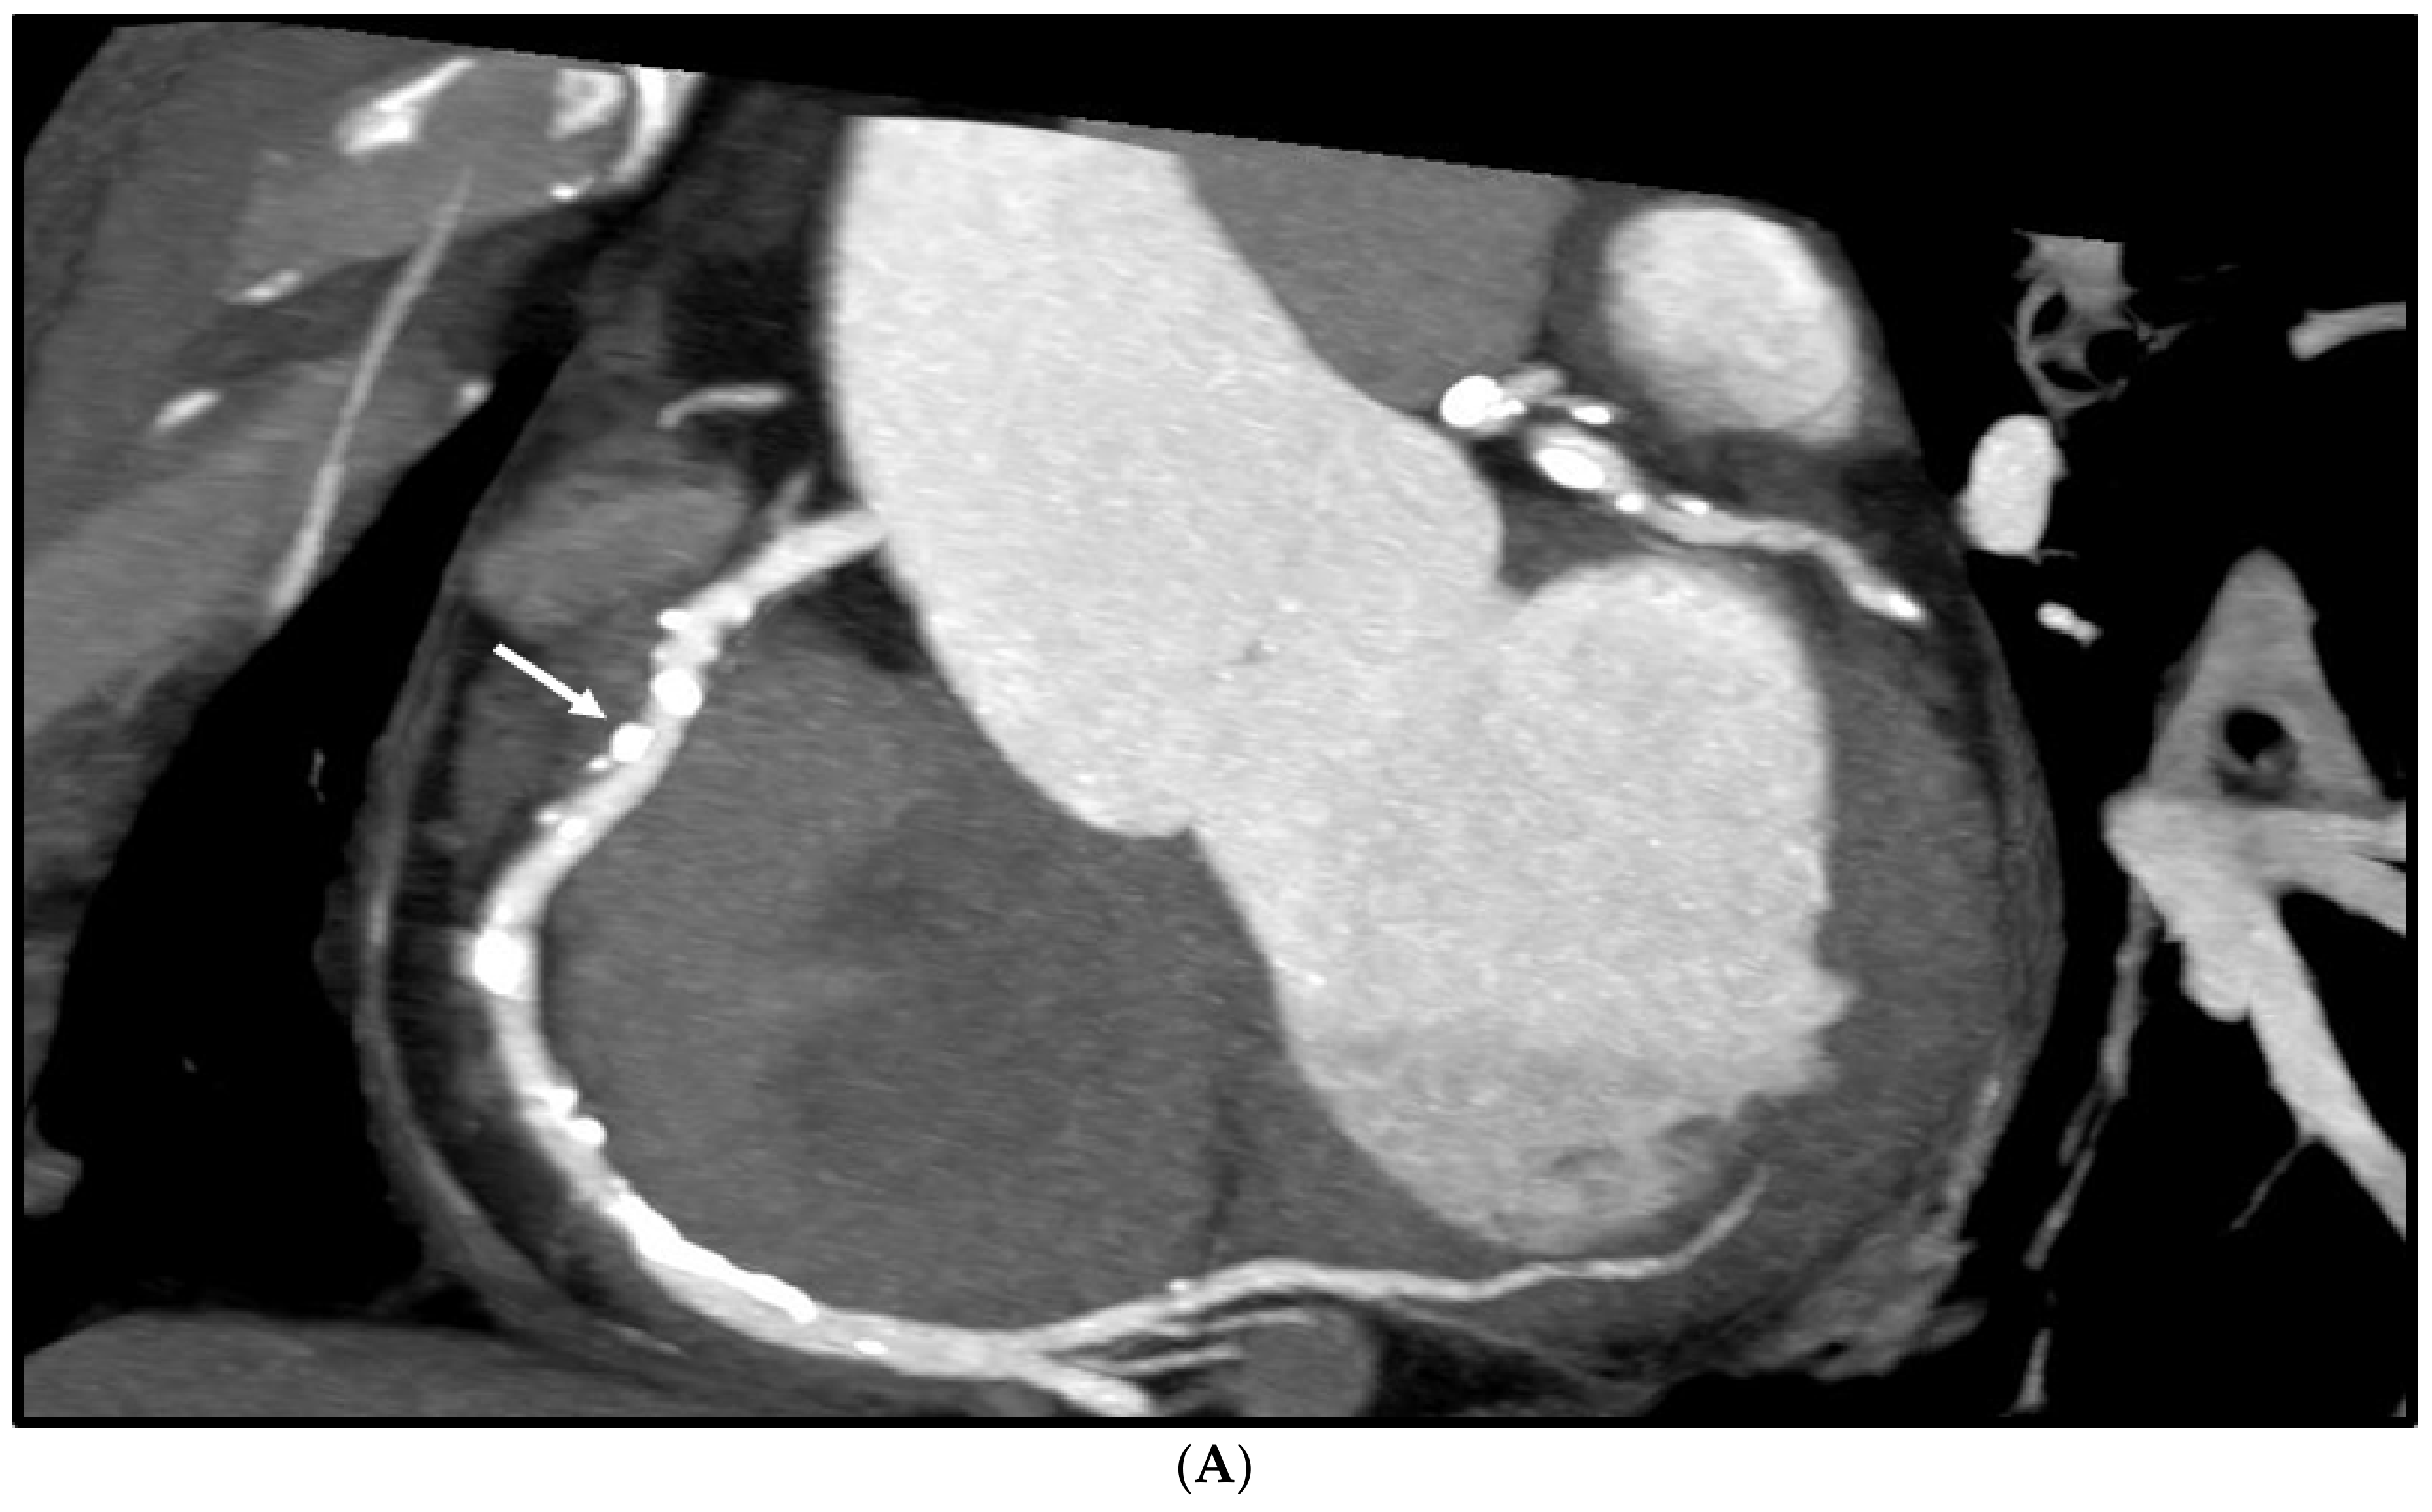

1. Introduction

2.2. Deblooming in CCTA

2.5. Reduction of Blooming Artifact by ESRGAN